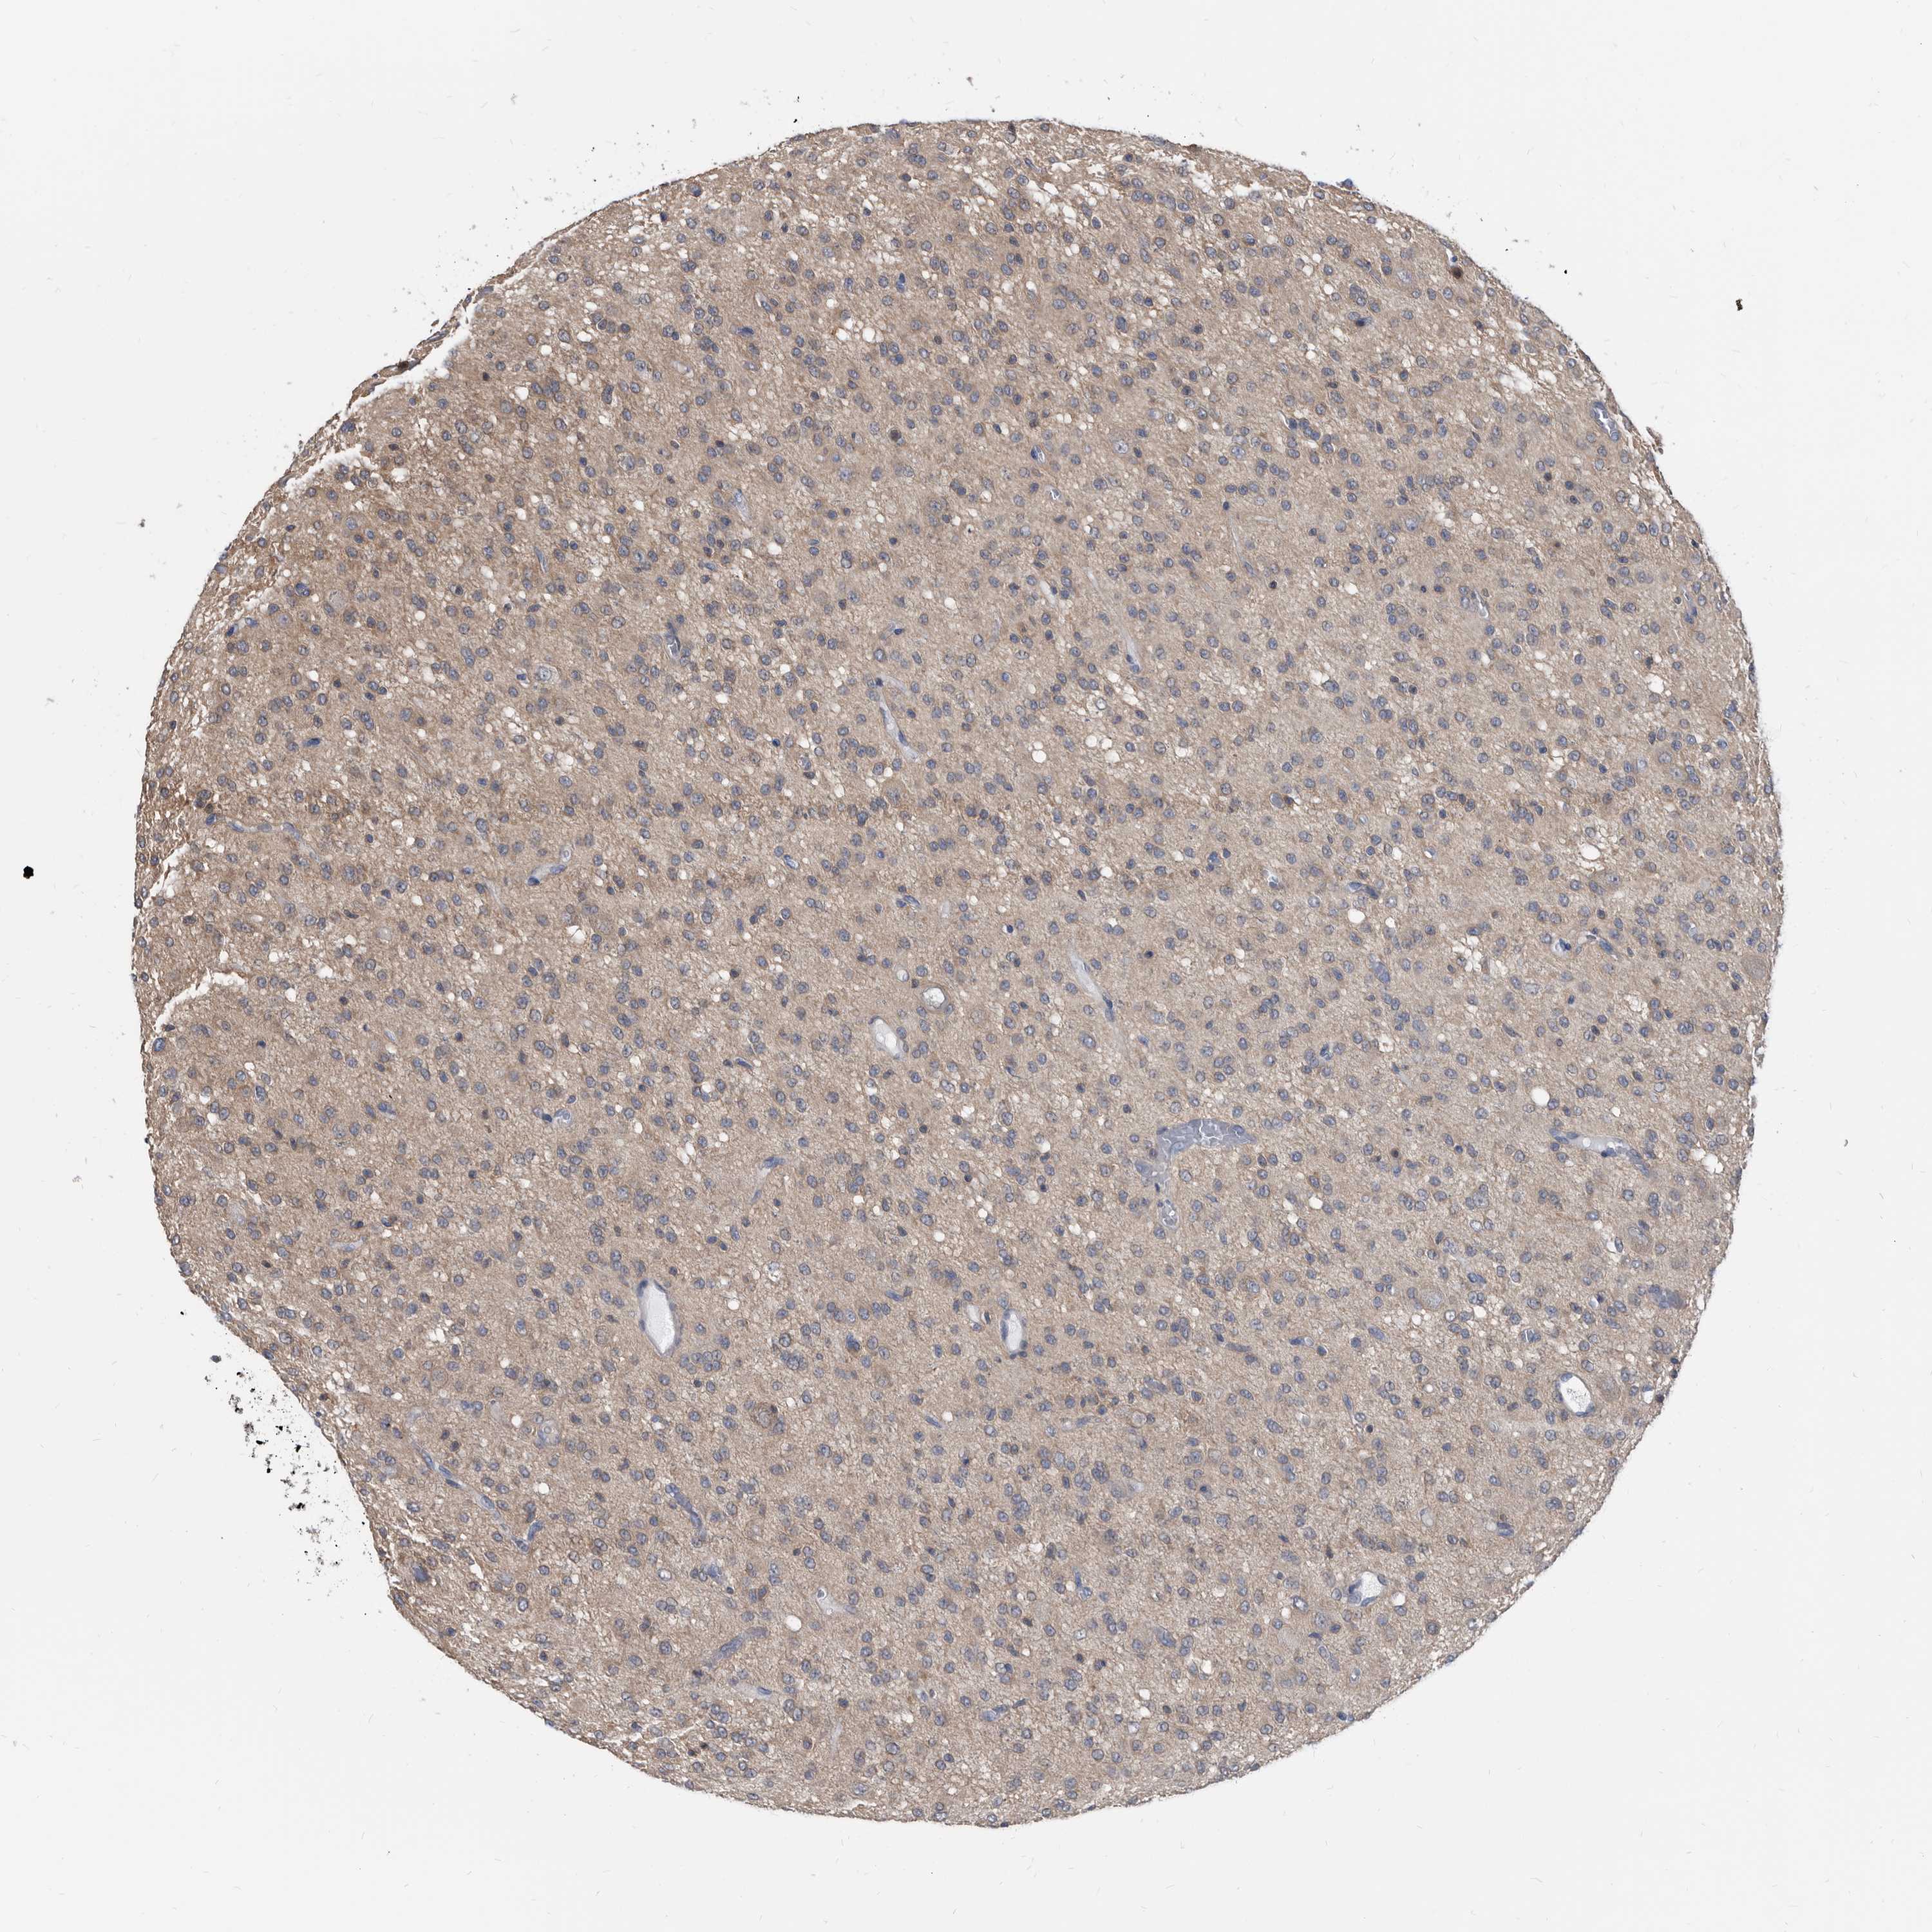

GLIOMA - Protein expressioni

A mouse-over function shows sample information and annotation data. Click on an image to view it in a full screen mode. Samples can be filtered based on level of antibody staining by selecting one or several of the following categories: high, medium, low and not detected. The assay and annotation is described here.

Note that samples used for immunohistochemistry by the Human Protein Atlas do not correspond to samples in the TCGA dataset.

Antibody stainingi

Antibody staining in the annotated cell types in the current human tissue is reported as not detected, low, medium, or high, based on conventional immunohistochemistry profiling in selected tissues. This score is based on the combination of the staining intensity and fraction of stained cells.

Each image is clickable and will lead to virtual microscopy that enables deeper exploration of all samples and also displays staining intensity scores, fraction scores and subcellular localization as well as patient and tissue information for each sample.

Antibody HPA029700

Antibody HPA029701

Antibody HPA029702

Antibody HPA029703

Staining

High

Medium

Low

Not detected

Intensity

Strong

Moderate

Weak

Negative

Quantity

>75%

75%-25%

<25%

None

Location

Nuclear

Cytoplasmic/membranous

Cytoplasmic/membranous,nuclear

Glioma, malignant, High grade

Glioma, malignant, Low grade

Glioblastoma, NOS